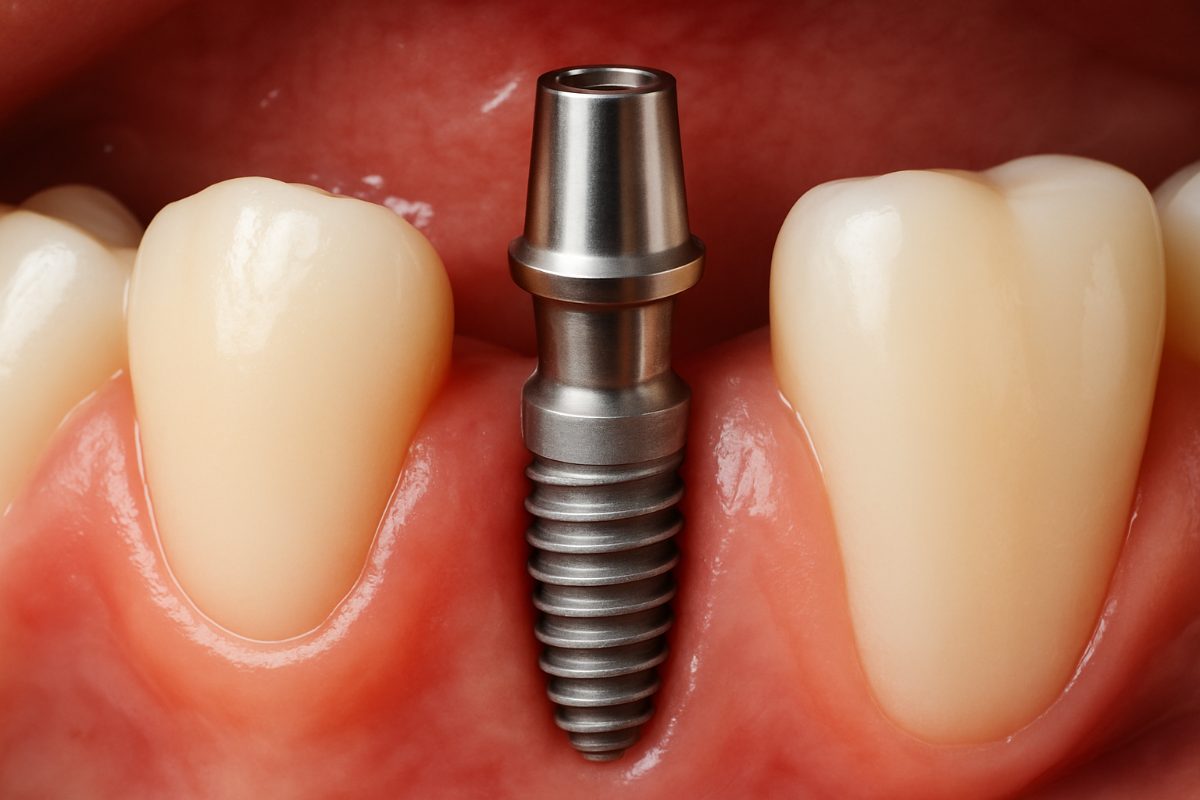

Illustration of a tooth implant being placed into a jawbone, with a clear view of the implant's components (screw, abutment, and crown). No text on image.